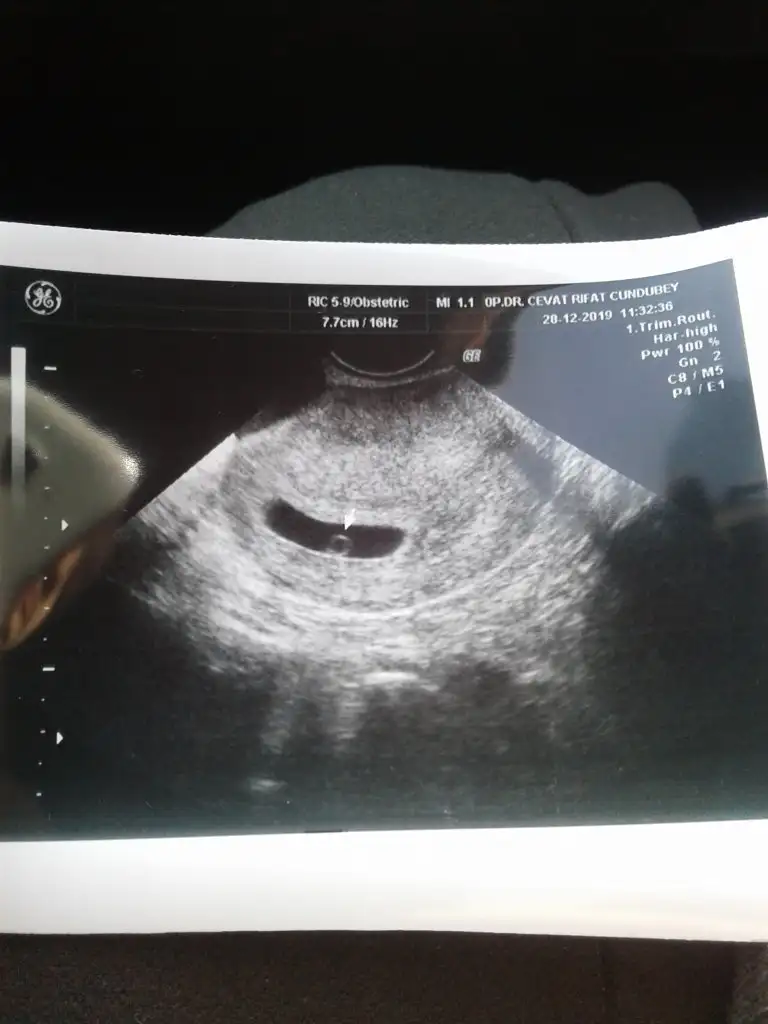

2 hafta sonraya cnm bugün 5+3normal bence cnm

Şimdi gördüm canım maşallah keseyi de bebişi de gördün mü yani ben 5+1 de gidecegim kese için2 hafta sonraya cnm bugün 5+3

Inş sende görürsün cnm yakın zamandaŞimdi gördüm canım maşallah keseyi de bebişi de gördün mü yani ben 5+1 de gidecegim kese için![]()

Benim rahim ters vajinal baktı ve bebegide gördük ben 5+3um bugun